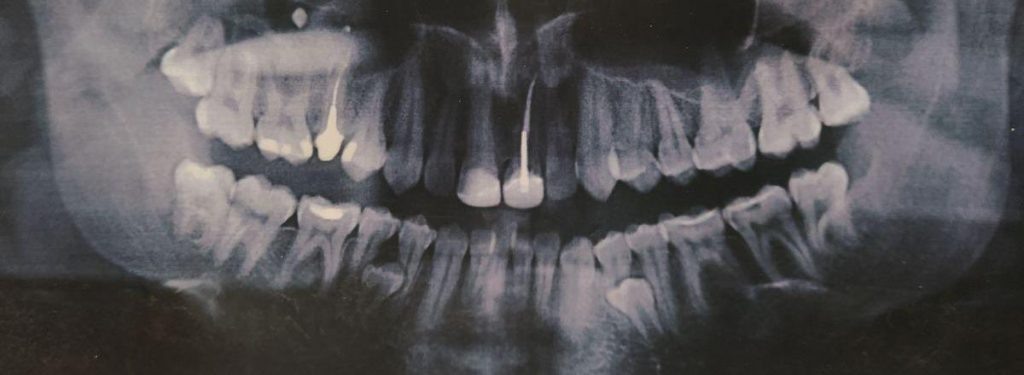

Мои зубы в 16 лет. На фото видно уже почти сформировавшиеся сверхкомплектные четверки и уже кривые зубы снизу

В 16 лет я увидел панорамный снимок на фото выше и, уже успев натерпеться стоматологии и врачей, я загрустил (я только что сильно болел фронтитом и гайморитом в 15 лет, в 7 классе только перестав носить пластинку, я побежал, споткнулся и выбил передние зубы о бетонную плиту). Я спросил врача в Красноярске, который анализировал снимок, мол что же делать с лишними зубами (а тогда они еще не особо мешали и только слегка прощупывались)? Я получил довольно точный ответ в духе – нужно надрезать десну, отворачивать ее, сверлить кость и удалять зубы. Это меня впечатлило настолько, что я отложил решение этого вопроса аж до 29 лет. Да и не до этого как-то было.